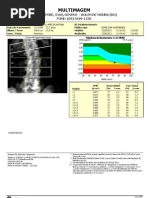

Densitometria ssea Pode detectar massa ssea baixa antes que uma fratura ocorra, confirmar um diagnstico de osteoporose, determinar a perda ssea e monitorar os efeitos do tratamento.

Quanto mais baixo for o T-score, maior a gravidade da osteoporose e maiores os riscos de fraturas.

Mulheres acima de 65 anos, em ps-menopausa que apresentem fatores de risco e em homens com fatores de risco importantes.